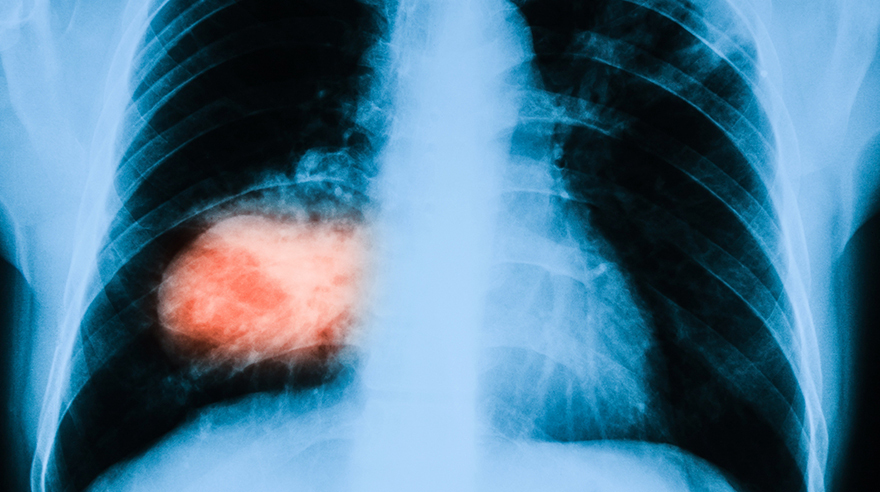

Даже если вы никогда не курили, всё равно есть вероятность, что у вас возникнет рак лёгких. Так утверждает доктор Мисак Хайгенц-младший. Подробнее – в статье.

Несмотря на то что главная причина рака лёгких – курение, даже те, кто не курит, подвержены риску рака. По словам доктора Мисак Хайгенц-младшего, заведующего отделением торакальной онкологии и онкологии головы и шеи в Институте рака Рутгерса в Нью-Джерси в Нью-Брансуике, заболеть этим видом рака может кто угодно, у кого есть лёгкие.

Кроме того, как показало недавнее исследование Национального института рака США, из всех испытуемых у 10% мужчин и 20% женщин возник рак лёгких, хотя они никогда не курили. Также, как утверждается в этом исследовании, некурящие подвержены трём типам рака лёгких.

Рак лёгких у людей, которые даже не начинали курить, возникает из-за пассивного курения, воздействия радона, асбеста. Хайгенц подчёркивает, что всё, что вдыхает человек, может спровоцировать рак. Причём подобные вредные компоненты определены ещё не все.